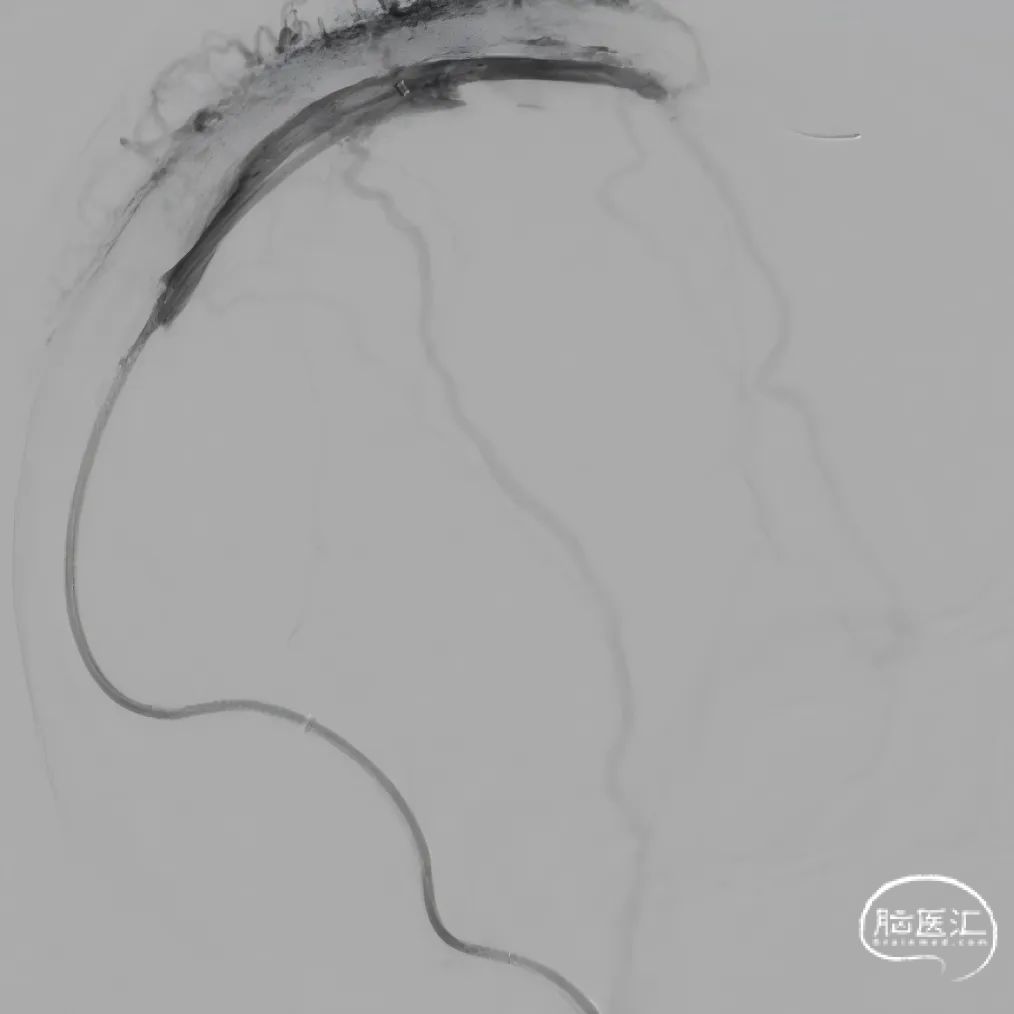

股动脉穿刺置5F鞘做静脉窦造影,股静脉穿刺置8F鞘进行治疗。260cm泥鳅导丝,将132cm 0.068" React™导管送至上矢状窦前部,尽量推高长鞘,增加支撑力。

经中间管手推造影,确认血栓位置。

单纯抽吸难以实现良好再通,经300cm微导丝长交换送入115cm Navien™颅内支撑导管;选用5*30mm球囊扩张,碎栓。

球扩后造影,上矢状窦接触溶栓尿激酶20万U。

球囊扩张和接触溶栓后,再次经中间管反复抽吸后复查造影。

再次给予尿激酶10万U后复查造影。